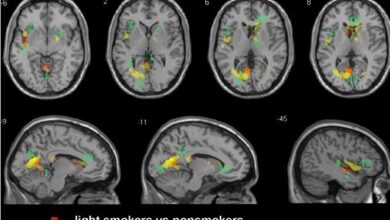

سگریٹ نوشی دماغ کو سکڑتی ہے

سائنسی شواہد سے پتہ چلتا ہے کہ سگریٹ نوشی دماغ کو سکڑتی ہے۔ ایک حالیہ تحقیق میں بتایا گیا ہے…